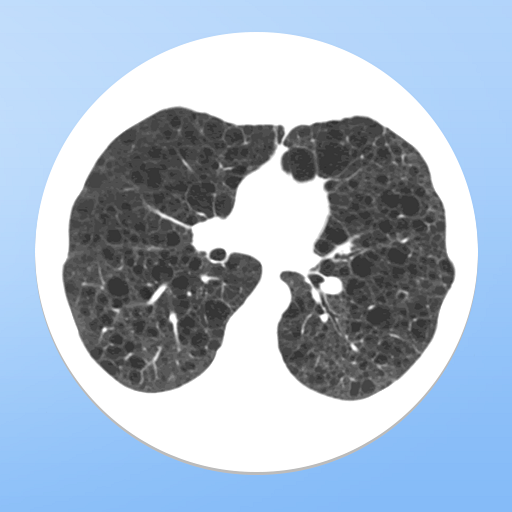

Stay up-to-date the easy way in pulmonary and critical care medicine, and upgrade the care you give your patients. PulmCCM's continuous literature review helps you keep up with the standard of care for respiratory conditions including COPD, asthma, pulmonary embolism, pulmonary fibrosis, and pulmonary hypertension, and critical illness including ARDS, sepsis, and septic shock.

If you work in an ICU or care for patients with lung disease, download the free app today to see what you've been missing: "all the best in pulmonary and critical care."